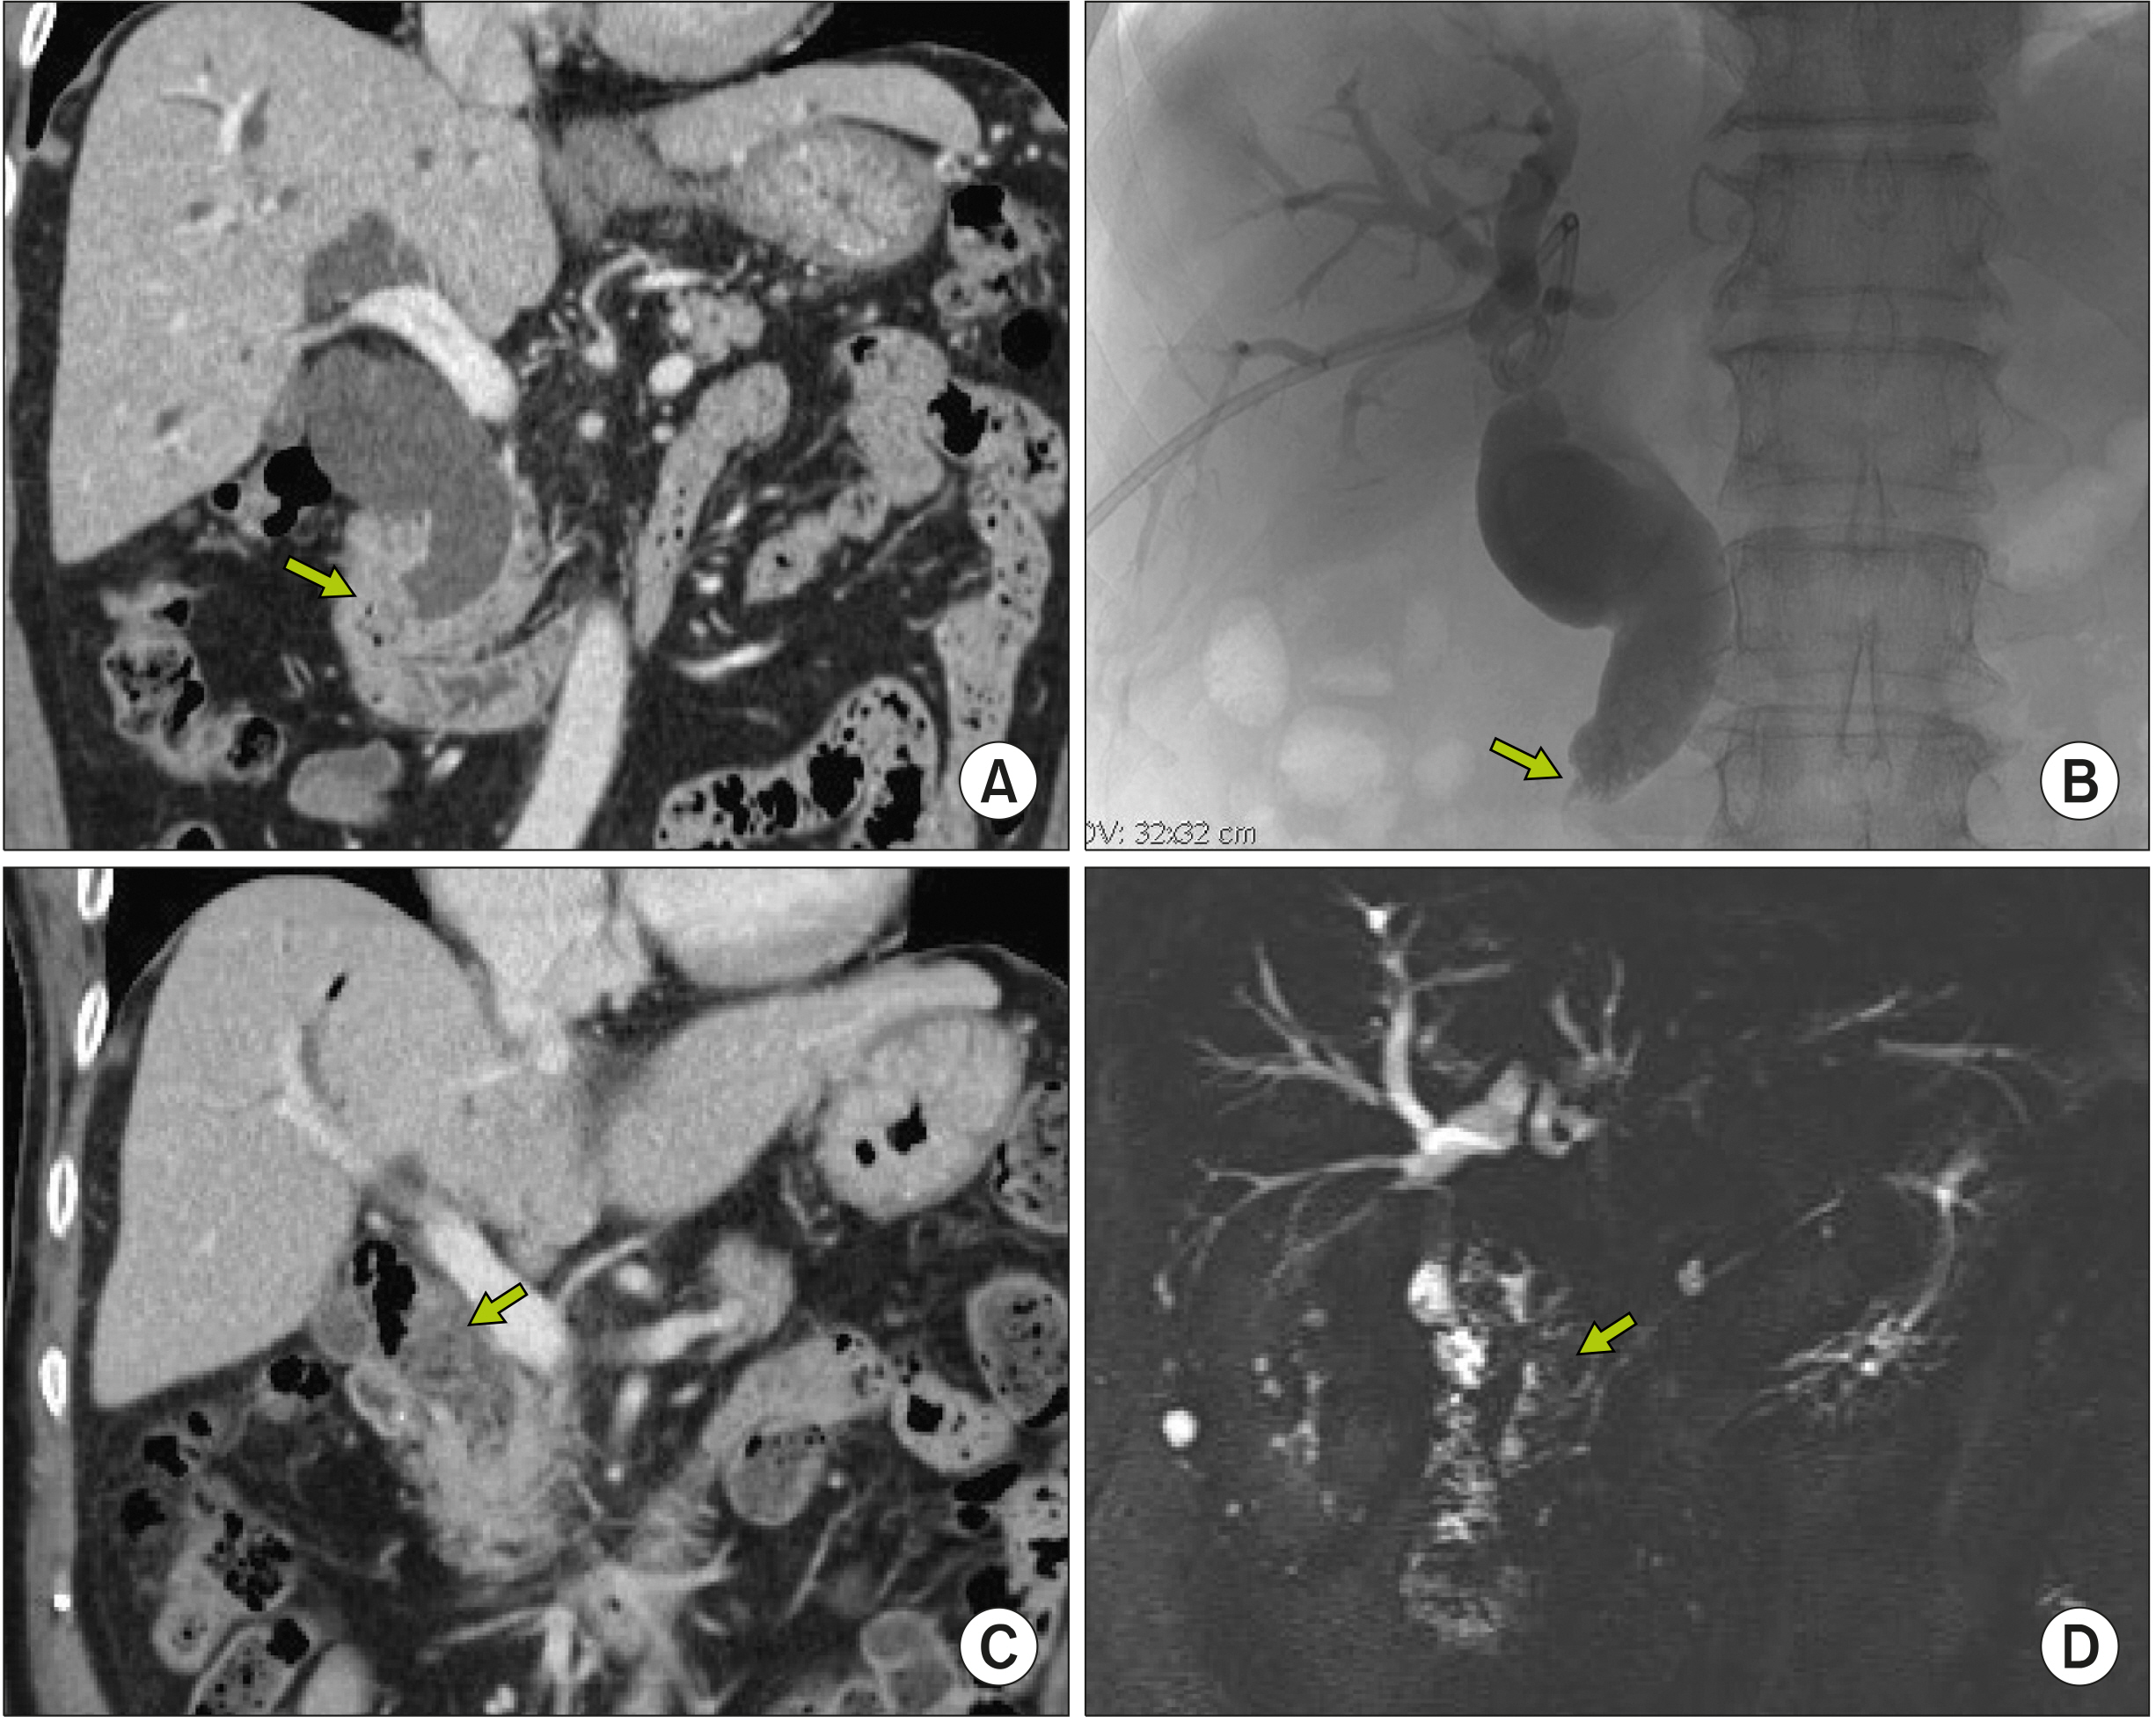

- Despite development in endoscopic treatment and minimally invasive surgery for choledocholithiasis, there remains a small number of patients who require bypass Roux-en-Y choledochojejunostomy (RYCJ) because of the intractable occurrence of common bile duct (CBD) stones. We herein present the detailed procedures of open RYCJ customized for intractable choledocholithiasis. The first method is a side-to-end choledochojejunostomy with intraluminal closure of the distal CBD. This method was applied to a 79-year-old female patient who underwent endoscopic retrograde cholangiopancreatography (ERCP) more than 10 times in the past 14 years (Case No. 1). The distal CBD was explored through choledochotomy and then the distal CBD lumen was occluded with internal running sutures. A large-sized choledochojejunostomy was performed. The patient recovered uneventfully and has been doing well for the past 2 years. The second method is an end-to-end choledochojejunostomy with segmental CBD resection. It was applied to a 75-year-old male patient who underwent ERCP 9 times in the past 10 years (Case No. 2). The CBD was resected segmentally and a large-sized choledochojejunostomy was performed. The patient also recovered uneventfully and has been doing well for the past 2 years. In conclusion, the primary indication of bypass RYCJ is intractable choledocholithiasis which requires numerous sessions of endoscopic stone removal over a long period. Open RYCJ is the preferred procedure to date. If the papilla is patulous, the distal CBD should be occluded or resected to prevent reflux ascending cholangitis. We recommend to resect the intrapancreatic distal CBD if it is markedly dilated like choledochal cyst.